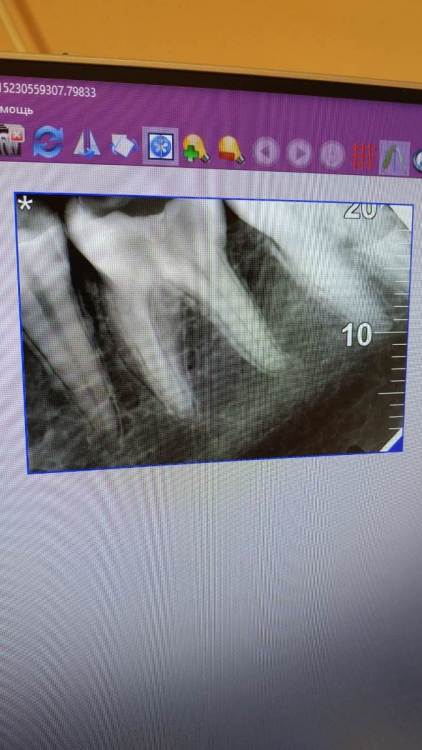

cinnamonbun Опубликовано 27 декабря, 2023 Поделиться Опубликовано 27 декабря, 2023 Изначально жалоб на зуб (нижняя шестерка) не было, пришла просто вылечить кариес. Пролечили, поставили пломбу, Через два месяца зуб внезапно начал болеть при надкусывании, немного реагировал на холодное и горячее. Попала к другому врачу, решили депульпировать зуб, прочистили каналы, поставили мышьяк. Через два дня должны были убрать лекарство и поставить пломбу, но боль при надкусывании не исчезла, поэтому врач отправил ждать ещё неделю, с тем же лекарством. Пришла через неделю, зуб всё ещё болит. Врач повторно зачистила каналы, поменяла лекарство, отправила ждать на две недели. И вот, вчера был уже четвертый приём, зуб всё ещё болел. Сделали снимок, определили проблемный канал (рядом с пятеркой), расширили его и снова зачистили, поставили антисептик. Врач уже разводит руками и говорит, что "ничего болеть не должно и чистить там нечего", назначила только пропить нимесил. Сказала, что после всех этих манипуляций, на следующий день (сегодня) он уже не должен болеть. Но зуб все так же продолжает болеть при надкусывании, как и в начале. Я уже в каком-то отчаянии. Какие могут быть причины, что это может быть? Визуально десна и зуб выглядят нормально, внешних воспалений/опухания нет, боль никуда не отдаёт. С депульпирования прошло три недели, болит именно шестерка, зубы рядом в порядке. Ссылка на комментарий

cinnamonbun Опубликовано 28 декабря, 2023 Автор Поделиться Опубликовано 28 декабря, 2023 @red_butler Добрый день, это снимок после лечения (сделан два дня назад), до того как заложили антисептик в канал и поставили временную пломбу Ссылка на комментарий

Carioznik Опубликовано 28 декабря, 2023 Поделиться Опубликовано 28 декабря, 2023 Сделайте КТ, в зубе, возможно, нестандартная анатомия каналов. Как вариант: есть дополнительный канал (который и является причиной) Ссылка на комментарий